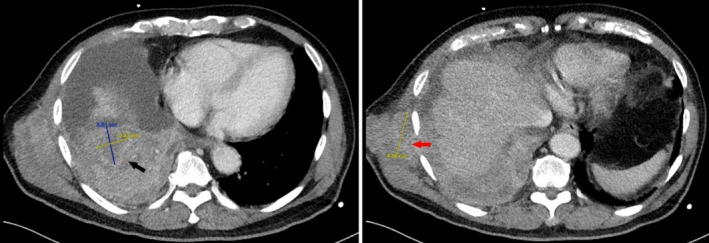

A 78-year-old man with a history of haemothorax developed a chest wall mass at the site of a previous chest drain 2 months ago. Imaging revealed a right lung mass with pleural involvement and a soft tissue tract to the chest wall. Histology confirmed squamous cell carcinoma. This case highlights a rare instance of metastasis via a chest drain tract.